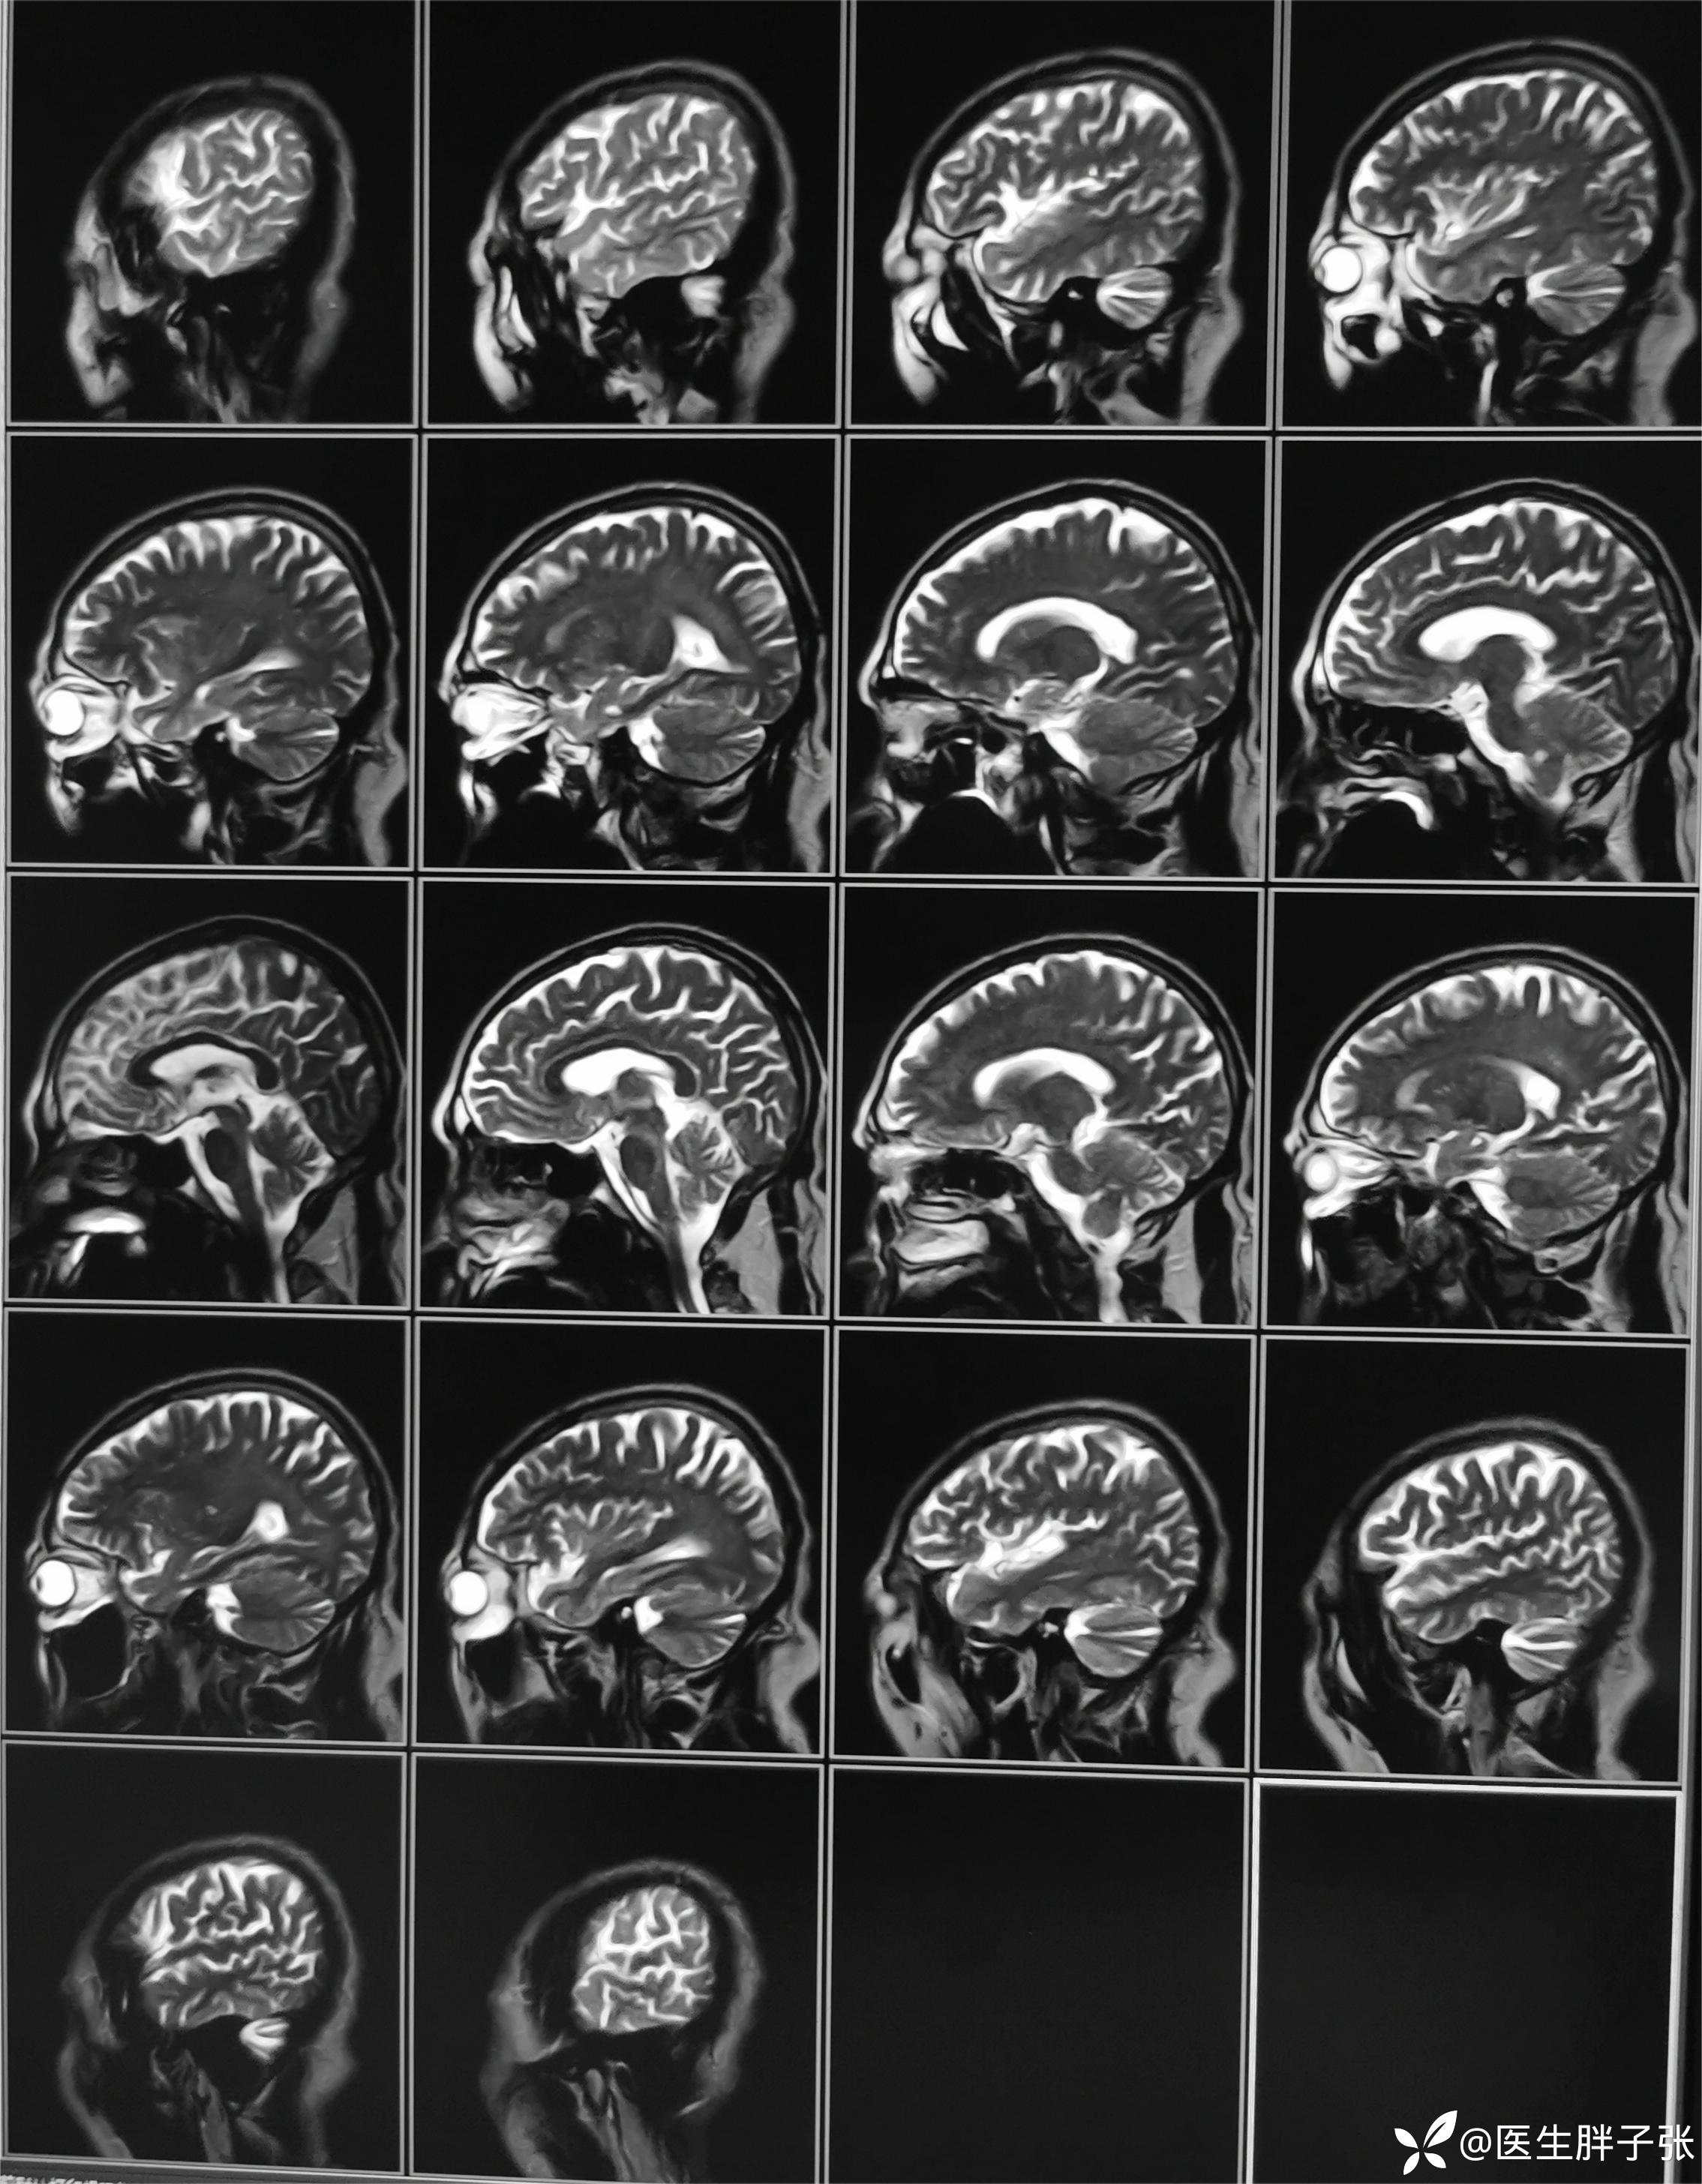

颅脑MR回报左侧顶叶新近梗死灶;多发腔隙性脑梗死及缺血灶;MRA未见异常。

再次查看核磁,考虑患者左侧顶枕叶及右侧枕叶脑组织存在混杂信号。

查房意见:颅脑MR存在顶叶新近梗死,椎动脉作为责任血管的梗死可能性大。患者存在前驱感染,需除外颅内感染、自免脑、副肿瘤可能。